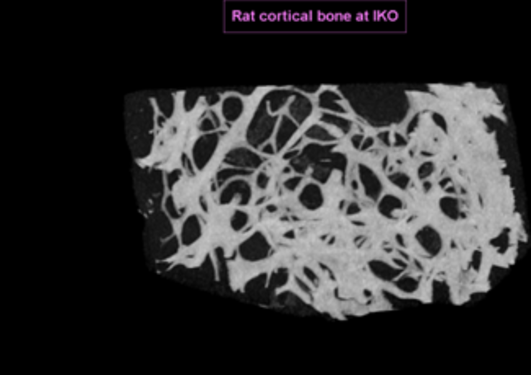

MicroCT

Odontologisk forskningslaboratorium har MicroCT som kan benyttes av både eksterne og interne forskere. Den er plassert på biologilaboratoriet i 4. etasje i Årstadveien 19.